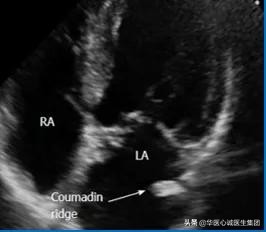

五、华法林嵴

对应于右心房的界嵴,是分隔左心耳和左上肺静脉的解剖结构。

食管超声断面图

牛角状的为患者的左心耳,上方为左上肺静脉。

二者间的隔膜为华法林嵴,类似棉签样改变。

超声心动图

可表现为Q尾征,见箭头处。

★★ 该结构是正常的,在临床诊疗过程中需要注意鉴别。

超声出现后,由于我们不认识该解剖结构,经常误诊为血栓之类的疾病,导致有些患者在早期时服用华法林(商品名Coumadin),因而得名。

上世纪80、90年代,日本学者曾提出“超声制造病”这一概念。指在没有超声检查之前,我们不知道某些疾病的存在。而在超声检查出现后,会把正常的结构误诊为疾病。界嵴和华法林嵴均属于超声制造病的典型代表,其实二者都是正常的解剖结构,但是被误诊为占位或血栓等。